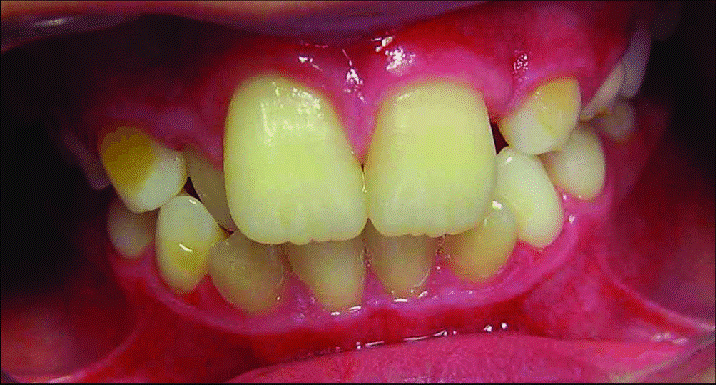

گاهی اوقات ممکن است فردی فک کوچکی داشته باشد و همین امر موجب شود دندان های او بزرگ به نظر برسد اما گاهی اوقات واقعا یک نفر دندان هایی بزرگتر از حد نرمال دارد. در واقع می توان گفت زمانی که یک نفر دندان هایی دارد که اندازه آن ها نسبت به هم سن و سالان و همجنس های خود خیلی بزرگتر باشد، مبتلا به بیماری به نام ماکرودنشیا خواهد بود. ماکرودنشیا در واقع به حالتی گفته می شود که فردی نسبت به سایر هم سن و سالان و هم جنس های خود دندان هایی بزرگتر داشته باشد. 3/0 تا 9/1 درصد از افراد در سراسر جهان مبتلا به بیماری ماکرودنشیا هستند.

جالب است بدانید در این افراد همه دندان ها بزرگتر از حد نرمال نخواهد بود، بلکه غالباً بیماران مبتلا به ماکرودنشیا تنها یک یا دو دندان بزرگتر از دندان های نرمال خواهند داشت. برای مثال گاهی اوقات دو دندان در کنار هم و به صورت چسبیده با هم رشد می کنند و همین امر موجب می شود یک دندان فوق العاده بزرگ در ظاهر ایجاد شود. در برخی موارد هم دندان هایی تکی و منفرد به صورت غیر طبیعی در اندازه بزرگ رشد می کنند. غده هیپوفیز افراد مبتلا به ماکرودنشیا بزرگتر از اندازه معمول در سایر افراد است و همین امر موجب بزرگ شدن همه اجزای صورت فرد می شود. ماکرودنشیا دلایل مختلفی دارد که از آن جمله می توان به عوامل ژنتیکی و محیطی، نژادی و هورمونی اشاره کرد. جالب است بدانید ماکرودنشیا بیشتر در میان مردان و آن هم در ناحیه آسیا اتفاق می افتد.